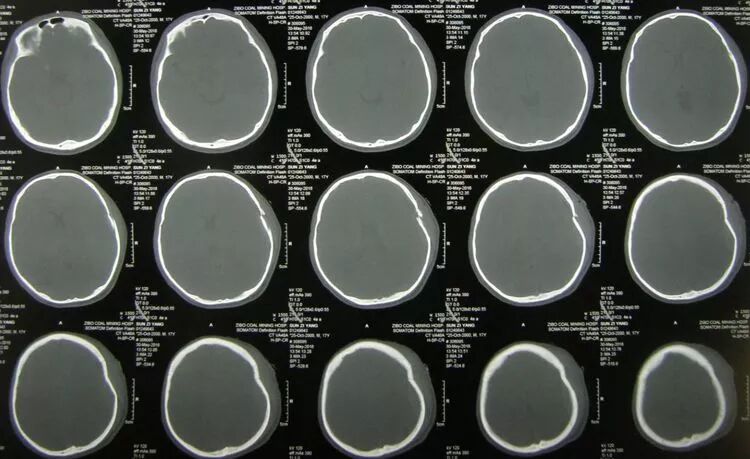

患儿女,12岁,头部车祸伤2小时入院,浅昏迷状,右额部纵形锯齿状裂口,前自眉弓延伸至发际内,可见骨折裂隙。右瞳孔欠规则。

CT示:

右额叶脑挫裂伤,蛛网膜下腔出血,颅内积气,额骨及前颅底骨粉碎骨折,基底池模糊。